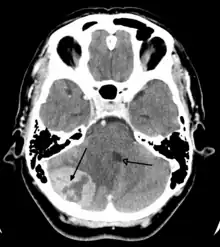

Imaging

Medical imaging plays a central role in the diagnosis of brain tumors. Early imaging methods – invasive and sometimes dangerous – such as pneumoencephalography and cerebral angiography have been abandoned in favor of non-invasive, high-resolution techniques, especially magnetic resonance imaging (MRI) and computed tomography (CT) scans,[38] though MRI is typically the reference standard used.[41] Neoplasms will often show as differently colored masses (also referred to as processes) in CT or MRI results.

- Benign brain tumors often show up as hypodense (darker than brain tissue) mass lesions on CT scans. On MRI, they appear either hypodense or isointense (same intensity as brain tissue) on T1-weighted scans, or hyperintense (brighter than brain tissue) on T2-weighted MRI, although the appearance is variable.

- Contrast agent uptake, sometimes in characteristic patterns, can be demonstrated on either CT or MRI scans in most malignant primary and metastatic brain tumors.

- Pressure areas where the brain tissue has been compressed by a tumor also appear hyperintense on T2-weighted scans and might indicate the presence of a diffuse neoplasm due to an unclear outline. Swelling around the tumor known as peritumoral edema can also show a similar result. This is because these tumors disrupt the normal functioning of the BBB and lead to an increase in its permeability.

Computed Tomography (CT) Scan – uses x-rays to take pictures from different angles and computer processing to combine the pictures into a 3D image. A CT scan usually serves as an alternative to MRI in cases where the patient cannot have an MRI due to claustrophobia or pacemaker. Compared to MRI, a CT scan shows a more detailed image of the bone structures near the tumor and can be used to measure the tumor’s size.[48] Like an MRI, a contrast dye may also be injected into the veins or ingested by mouth before a CT scan to better outline any tumors that may be present. CT scans use contrast materials that are iodine-based and barium sulfate compounds. The downside of using CT scans as opposed to MRI is that some brain tumors do not show up well on CT scans because some intra-axial masses are faint and resemble normal brain tissue. In some scenarios, brain tumors in CT scans may be mistaken for infarction, infection, and demyelination. To suspect that an intra-axial mass is a brain tumor instead of other possibilities, there must be unexplained calcifications in the brain, preservation of the cortex, and disproportionate mass effect.[49]